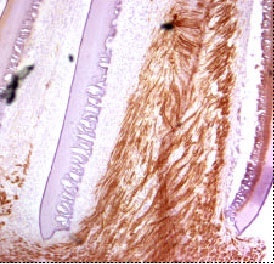

Sie besteht aus Chitosan, einem Abkömmling von Chitin aus Insektenpanzern. Das Material ist Protein-frei und induziert daher im Körper keine Abstoßungsreaktionen; es wird nach acht Wochen im Gewebe abgebaut. Die Schiene ähnelt einem Streifen Cellophan-Papier. Das Röllchen wird auseinandergezogen und zwischen die durchtrennten Nervenenden gespannt. Wird es gelockert, rollt sich das elastische Band um die Stümpfe und paßt sich dabei wie eine Spirale ohne Druck der Nervendicke an. Der Wickel verbindet die Nervenenden und wird mit Fibrinkleber fixiert.

Zwischen den durchtrennten Enden wächst dann der Nerv durch den Tunnel der künstliche Scheidewand zusammen.

"Belegt wurde dies bei Ratten, denen ein Zentimeter aus dem Ischiasnerv entfernt worden war", so die Forscherin. Die Innervation der Muskeln durch den Nerv sei acht Wochen nach der Therapie demonstriert worden. Auch habe sich neues Bindegewebe um den zusammengewachsenen Nerv gelagert. Eine Neurombildung - die bei durchtrennten Nerven oft vorkommt - sei nicht registriert worden.